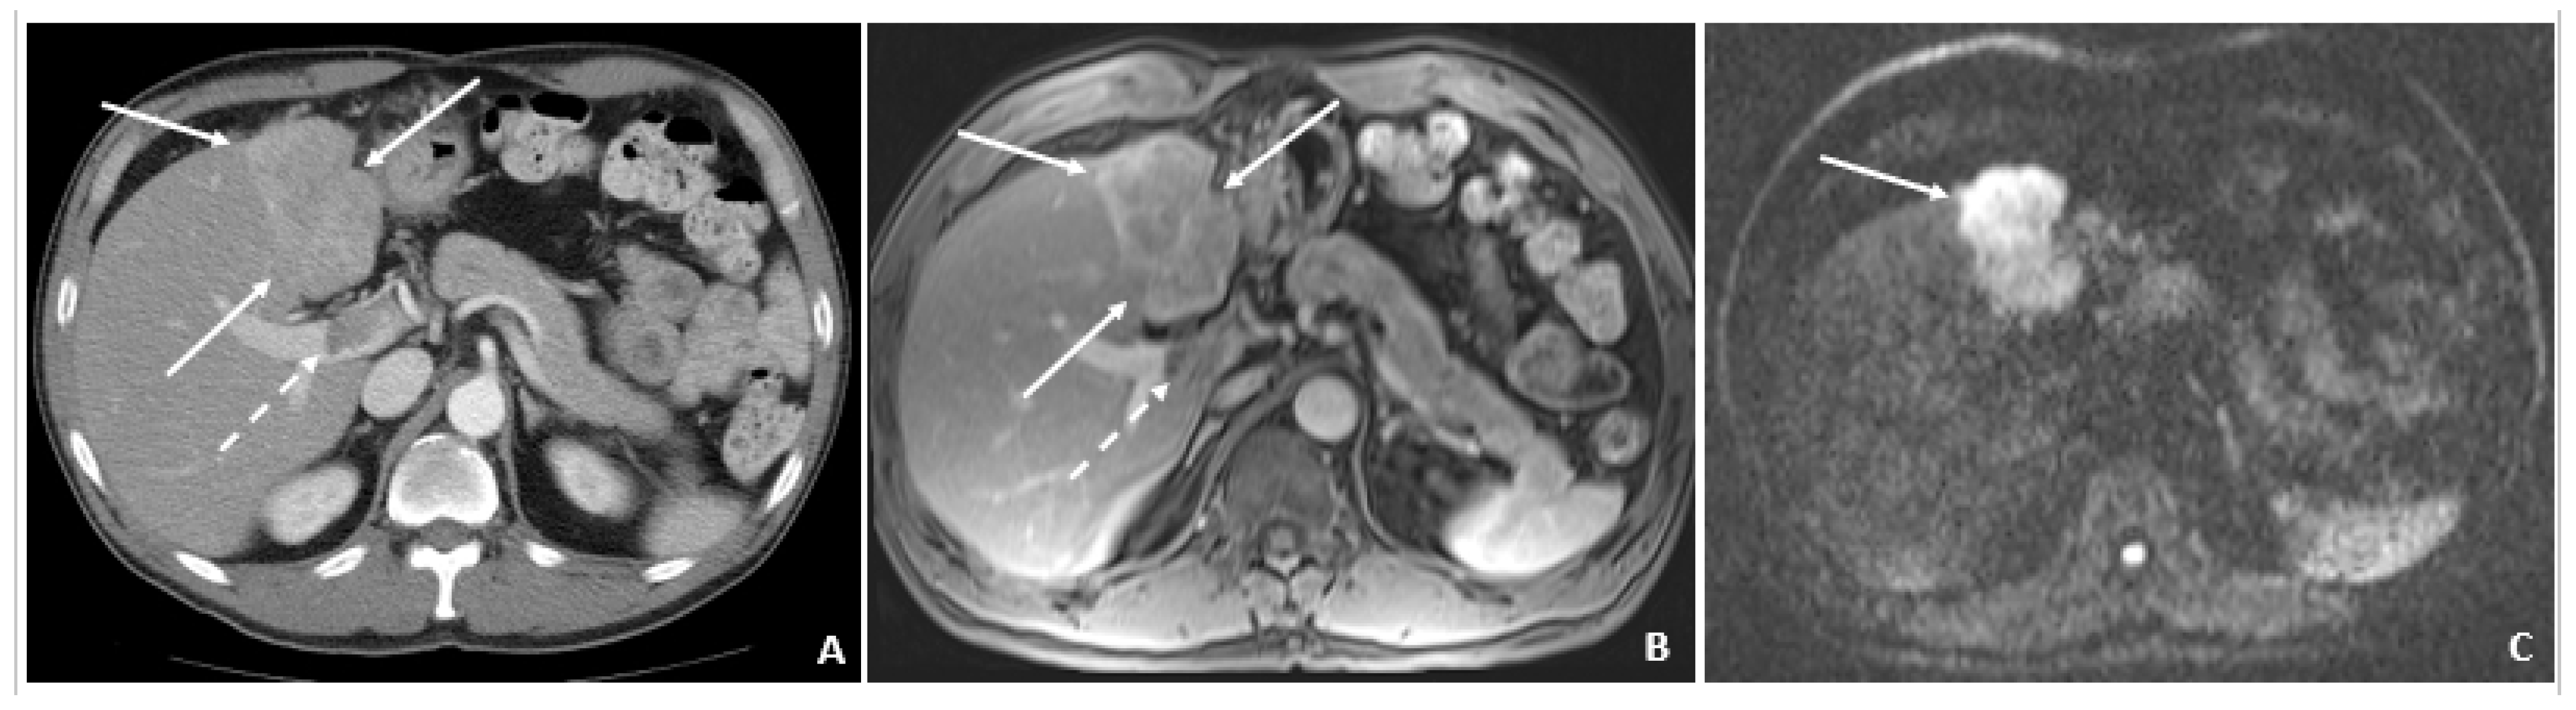

6.5. Case 5: A 58-Year-Old Male

A 58-year-old male was found to have CHB on a routine examination in May 2007. HBV DNA was 4.6 × 105 copies/mL. He was started on telbivudine. The AFP was 3.2 ng/mL in May 2008 with AFP-L3% of 13.8. The MRI in July 2008 showed cirrhosis and no tumor. In August 2008, the AFP remained low at 3.2 ng/mL, but there was a rise in the AFP-L3% to 33.6. The AFP-L3% continued to rise to 69.7 by November 2008, while the absolute AFP value remained at 7.9 ng/mL. In March 2009, the AFP rose to 24.1 ng/mL, and the AFP-L3% at this time was continuing to rise to 87.7. At this time, the abdominal MRI showed a 2.4 × 2.0 cm HCC. He underwent cryoablation followed by radiofrequency tumor ablation and TACE (March and August 2009). These values are outlined in Table 5.

Figure 5. Triphasic CT at the time of HCC diagnosis (March 2009). (A) The precontrast image shows a hypodense lesion (arrow) at the site of the punctate hyperenhancing lesion shown in Figure 4. (B) The corresponding arterial-phase postcontrast image reveals hyperenhancement (arrow). (C) The portal-phase postcontrast image shows washout (arrow), and all features are typical of HCC and confirm the diagnosis in the setting of chronic HBV.